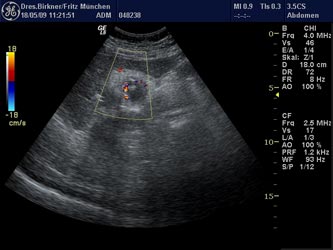

Die Untersuchung der Bauchorgane (Leber, Bauchspeicheldrüse, Gallenblase, Milz, Dickdarm, Magen, große Bauchgefäße und Nieren) mit Ultraschallgeräten wird als abdomineller Ultraschall bezeichnet. Die Untersuchung wird durch das Senden und Empfangen von Ultraschallwellen ermöglicht (Echolot-Prinzip). Die Bilder geben Aufschluss über Dichteveränderungen der Organe, die Rückschlüsse auf Erkrankungen der Organe zulassen. Unser eingesetztes Gerät der neuesten Technologi erlaubt die Darstellung des Blutflusses in Venen und Arterien (Doppler-Ultraschall) .Für die Untersuchung der Gallenblase sollte der Patient nüchtern sein (kein Essen, kein Trinken vor dem Untersuchungstermin).